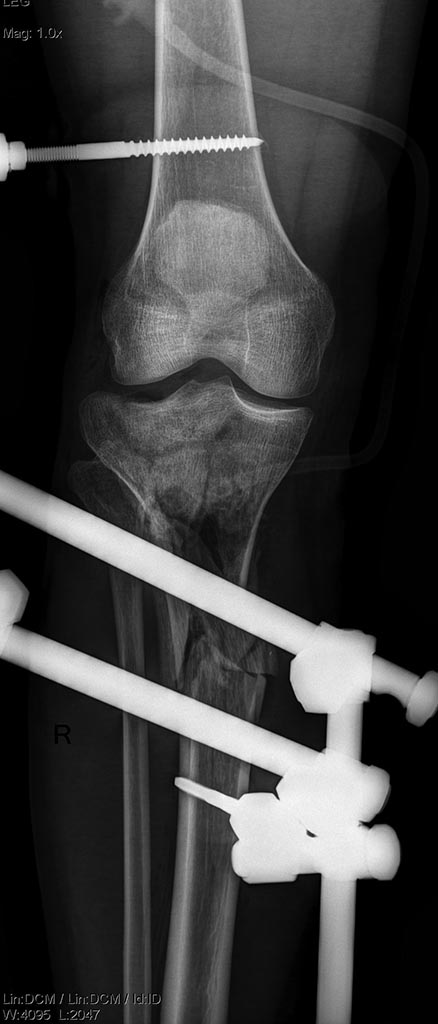

Имеется: Закрытый перелом диафиза левой локтевой кости. Закрытый оскольчатый перелом диафиза левой бедренной кости в средней трети. Открытые (3a-b) оскольчатые внутрисуставные переломы проксимального отдела обеих костей правой и левой голени. (см. снимки)

При поступлении выполнено: ПХО открытых перелом костей правой и левой голени, фиксация в аппаратах; фиксация перелома левой бедренной кости в аппарате; иммобилизация левого предплечья лонгетой.

Планируем: при неосложненном заживлении, остеосинтез правой большеберцовой кости пластиной; остеосинтез бедренной кости стержнем; локтевой кости пластиной.

Лечение АВФ. Но сделать максимально возможную дистракцию для компенсирования данного укорочения, а также это позволит более-менее вывести данные осколки в нужное положение. Ну и дальше до полной консолидации.